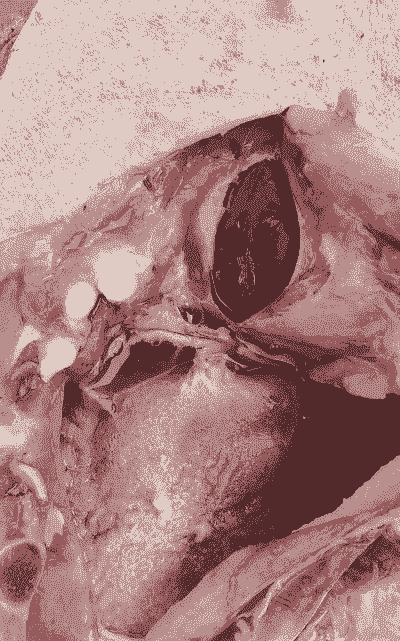

剖检病变:主要表现为胸膜炎、心包炎、腹膜炎、关节炎和脑膜炎,胸腹腔积液增多,有大量纤维素性渗出,心脏表面被覆纤维素性渗出物,俗称“绒毛心”。